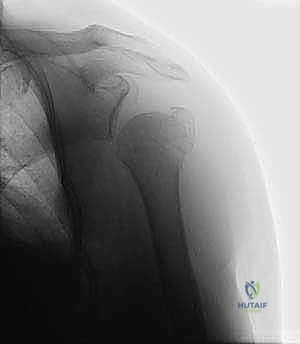

- الأشعة السينية (X-rays): يتم أخذ صور من زوايا متعددة (أمامية خلفية، جانبية، وإبطية) لتحديد نوع الكسر وموقعه.

- التصوير المقطعي المحوسب (CT Scan): في الكسور المعقدة (ثلاثية أو رباعية الأجزاء)، يُعد التصوير المقطعي ثلاثي الأبعاد ضرورياً جداً. فهو يمنح الجراح خريطة دقيقة لحجم الشظايا العظمية ومواقعها، مما يساعد في التخطيط الجراحي الدقيق قبل دخول غرفة العمليات.

في حالات الكسور المنزاحة التي تتطلب تدخلاً جراحياً، خاصة في الكسور ثنائية الأجزاء أو بعض الكسور ثلاثية الأجزاء، يُفضل الأستاذ الدكتور محمد هطيف استخدام تقنية التثبيت بالأسلاك عبر الجلد متى ما كانت مناسبة تشريحياً.

3. الرد المغلق للكسر (Closed Reduction)

بمهارة يدوية فائقة، يقوم الدكتور هطيف بإعادة الشظايا العظمية إلى مكانها التشريحي الصحيح عن طريق سحب الذراع وتدويرها بآليات محددة، كل ذلك تحت مراقبة الأشعة.